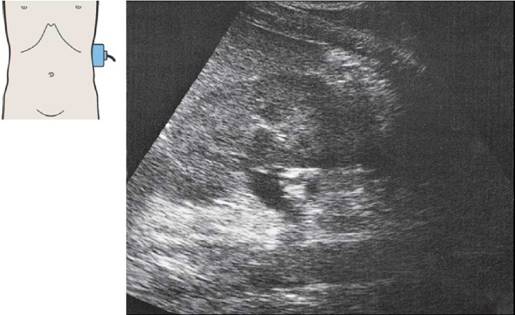

53 Печеночная артерия, воротная вена, нижняя полая вена

Сосуды ворот печени при поперечном сканировании

Воротная вена проходит между нижней полой веной и печеночной артерией.

Печеночная артерия в воротах печени отклоняется в цефалическом направлении.